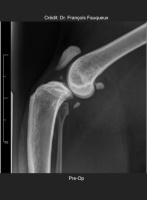

Radiologické snímky